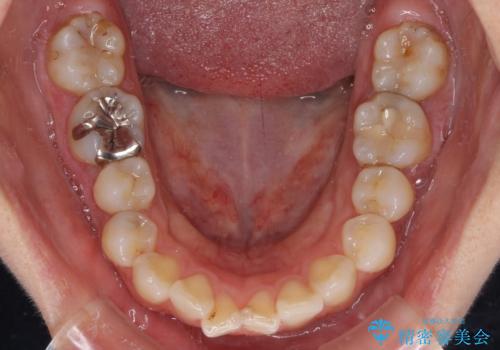

- 前歯のデコボコを治したいとのことで来院された患者様です。

上下顎ともに歯列全体の後方移動とIPR(歯と歯の間を削る)によってデコボコが解消するように設計し、インビザラインにより治療を行うこととしました。

しっかりと装着時間を守ってくださったのですが、途中妊娠にともなう悪阻や出産といったイベントがあり、予定よりも治療期間が長くなりました。